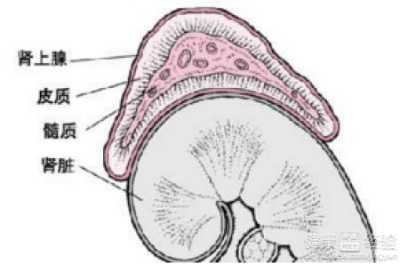

3,肾上腺——性腺综合征是比较常见的性早熟.